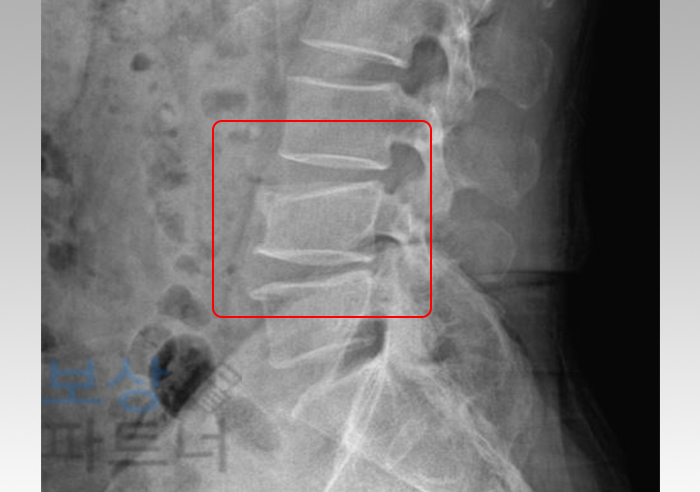

가장 주된 진단명은 요추 4번 압박골절 이었는데요. 위 엑스레이 사진을 보시면 척추뼈가 위아래로 찌그러지듯 골절된 것을 확인할 수 있습니다. 그런데 척추의 골절된 상태가 크게 불안정하지 않은 경우에는 보통은 수술 없이 허리보조기 착용하는 보존적 치료를 시행하게 됩니다.